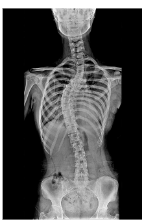

척추측만증 증상 원인 치료방법 및 검사방법 알아봐요. 척추측만증은 척추 디스크가 마모되어 디스크와 척추 사이의 신경뿐만 아니라 척추 자체가 변형되어 인접한 신경을 압박하여 통증, 근육 약화, 저림 등의 증상이 나타나는 질환입니다. 일반적으로 연령이 들수록 발생할 확률이 높아지며, 척추의 과도한 사용, 체중 부담 등이 원인이 될 수 있습니다. 치료는 약물 치료, 물리치료, 침술, 수술 등이 있으며, 정기적인 운동과 자세 관리도 중요합니다.

- X-ray 검사: 척추의 구조적인 문제나 변형을 확인하기 위해 사용됩니다. 비교적 저렴하고 간단한 검사 방법입니다.